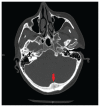

Traumatismes craniocérébraux et médullaires chez une piétonne heurtée par une trottinette électrique